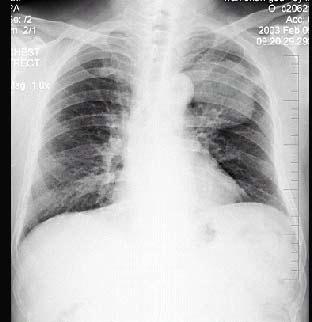

男性,70岁,因胸痛就诊,不咳嗽、发热,X线检查如图,最可能的诊断是 ( )A.左肺结核瘤B.左侧叶间积液C.左肺癌D.左肺炎性假瘤 ...

问题 男性,70岁,因胸痛就诊,不咳嗽、发热,X线检查如图,最可能的诊断是 ( )

选项 A.左肺结核瘤 B.左侧叶间积液 C.左肺癌 D.左肺炎性假瘤 E.支气管扩张

答案 C